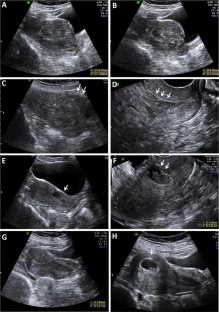

Cesarean scar pregnancy (CSP) is a rare kind of ectopic pregnancy implanted in the previous cesarean scar and has an increasing incidence over the past 30 years. As the suspicion is low, the diagnosis may be delayed or misinterpreted in ultrasound, leading to treatment strategies that might end up in uterine rupture or hysterectomy. The objective here is to review the ultrasound findings in CSP with varied presentations. Transabdominal and transvaginal sonography combined with color Doppler is a reliable tool for the diagnosis of CSP. When the gestational sac is seen in lower part of the uterine cavity, differentiation between threatened miscarriage, cervical pregnancy and CSP could be difficult. Not all cases of CSP present with typical ultrasound findings and a high index of suspicion is needed for diagnosis in these cases. An attempted curettage or MTP pill taken in an undiagnosed CSP often alters the typical findings. The possibility of CSP should also be considered in cases presenting with abnormal uterine bleeding and have a prior history of cesarean section. With lack of awareness about this condition, the diagnosis can often be missed either with MRI or in ultrasound. Correct interpretation and timely diagnosis save the mother from life-threatening complications and also preserves future fertility.

Fig. 1